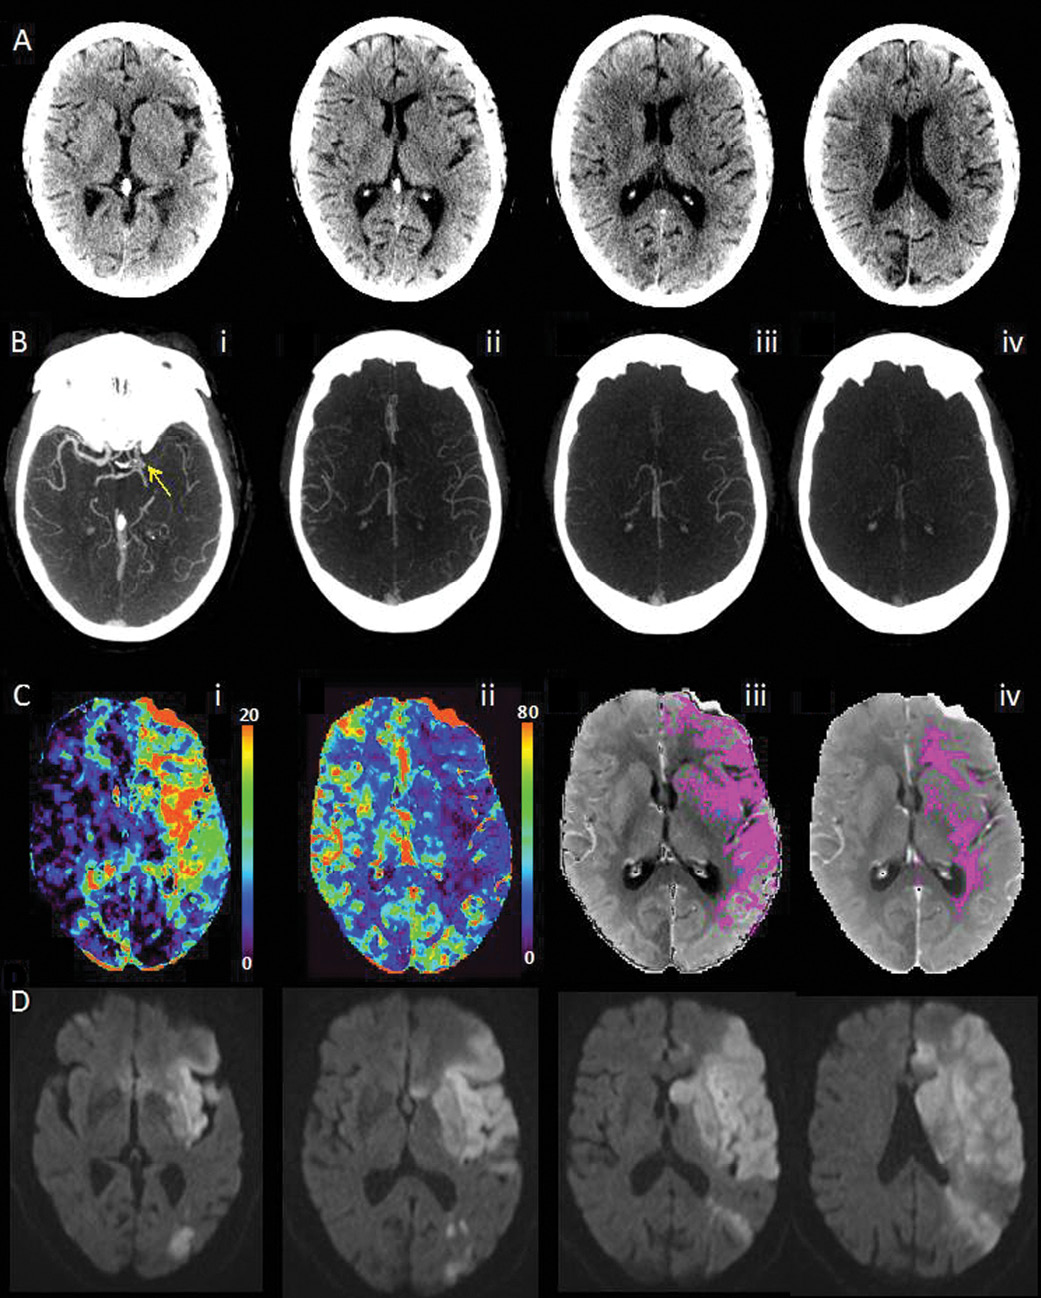

Researchers studied 147 acute ischemic stroke patients—all of whom underwent baseline unenhanced CT, single-phase CT angiography of the head and neck, perfusion CT and multiphase angiography CT, and compared techniques with respect to their interrater reliability and predictive ability. The mean patient age was 72 years and the patient cohort was about 50 percent male.

The authors independently assessed multiphase CT angiography in 30 randomly chosen subjects by using a six-point ordinal scale that was then reclassified into three clinically relevant categories ("good," "intermediate" and "poor" pial arterial filling). Researchers made treatment recommendations based on images using all scanning techniques.

In developing the multiphase CT angiography technique, researchers started with conventional arch-to-vertex CT angiography. The next two phases were sequential skull-base-to-vertex acquisitions performed in the mid- and late-venous phases. The result is three time-resolved images of pial arterial filling in the whole brain.